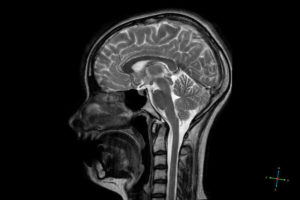

Ниже вы можете увидеть фото магнитно-резонансной томографии.

Чтобы лучше увидеть разницу между снимком МРТ с контрастом и без наведите курсор на фото и щёлкните по нему. В открывающимся окне вы сможете лучше рассмотреть отличия исследований.

Серия снимков МРТ головного мозга с применением контрастного вещества, сагиттальная и аксиальная проекции